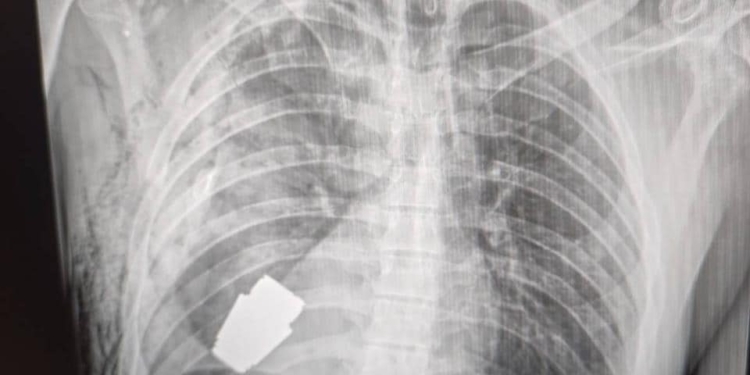

Військові лікарі провели операцію з видалення гранати ВОГ, яка не розірвалася, з тіла військовослужбовця. Її було видалено у присутності двох саперів, які страхували безпеку медичного персоналу.

Операція проводилася одним з найдосвідченіших хірургів ЗСУ Андрієм Вербою без електрокоагуляції, оскільки граната могла детонувати у будь-який момент.

Оперативне втручання пройшло успішно, а пораненого військовослужбовця було відправлено на подальшу реабілітацію та відновлення», – написала Ганна Маляр.